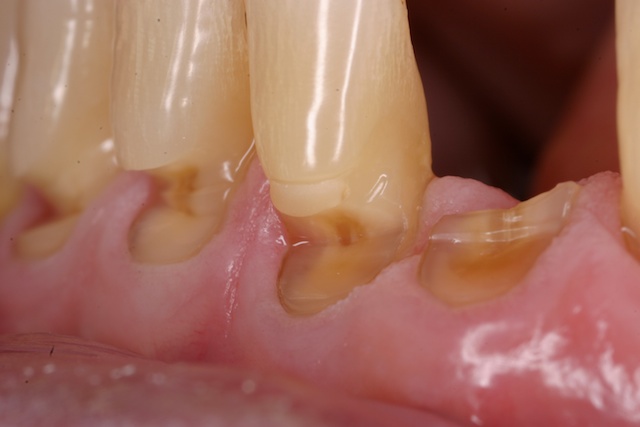

💡 핵심 요약: 치아와 잇몸이 맞닿는 ‘목 부분(치경부)’이 쐐기 모양으로 움푹하게 파여 상아질이 노출되면서 시린 통증을 유발하는 질환입니다.

보통 치아는 단단한 법랑질이 감싸고 있지만, 치경부는 구조적으로 법랑질이 얇고 힘이 집중되는 취약한 부위입니다. 이곳이 패이게 되면 외부 자극이 신경에 직접 전달되어 다음과 같은 증상이 나타납니다.

- 극심한 시림: 찬물, 뜨거운 음식, 심지어 찬바람에도 이가 찌릿합니다.

- 심미적 저하: 잇몸 라인이 패여 보여 치아가 길어 보이거나 형태가 변형되어 보입니다.

- 지속적 통증: 마모가 신경 근처까지 진행되면 가만히 있어도 통증이 느껴집니다.

- 플라그 축적: 패인 홈 사이로 음식물 찌꺼기와 세균막(플라그)이 잘 끼어 잇몸 염증과 부기를 유발합니다.